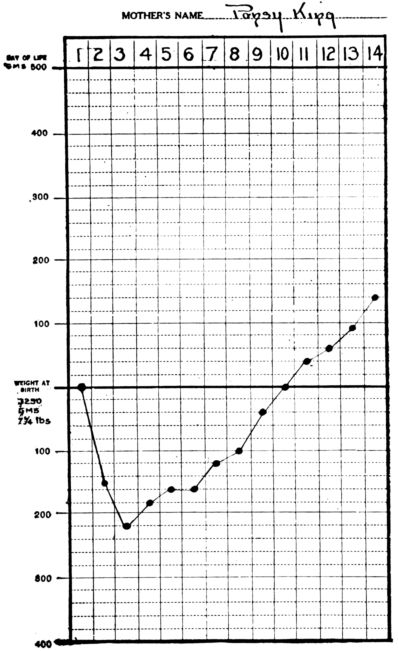

| 6. | Showing normal daily gain in weight during first two weeks | 520 |

| 7. | Showing loss of weight in inanition fever contrasted with No. 6 | 520 |